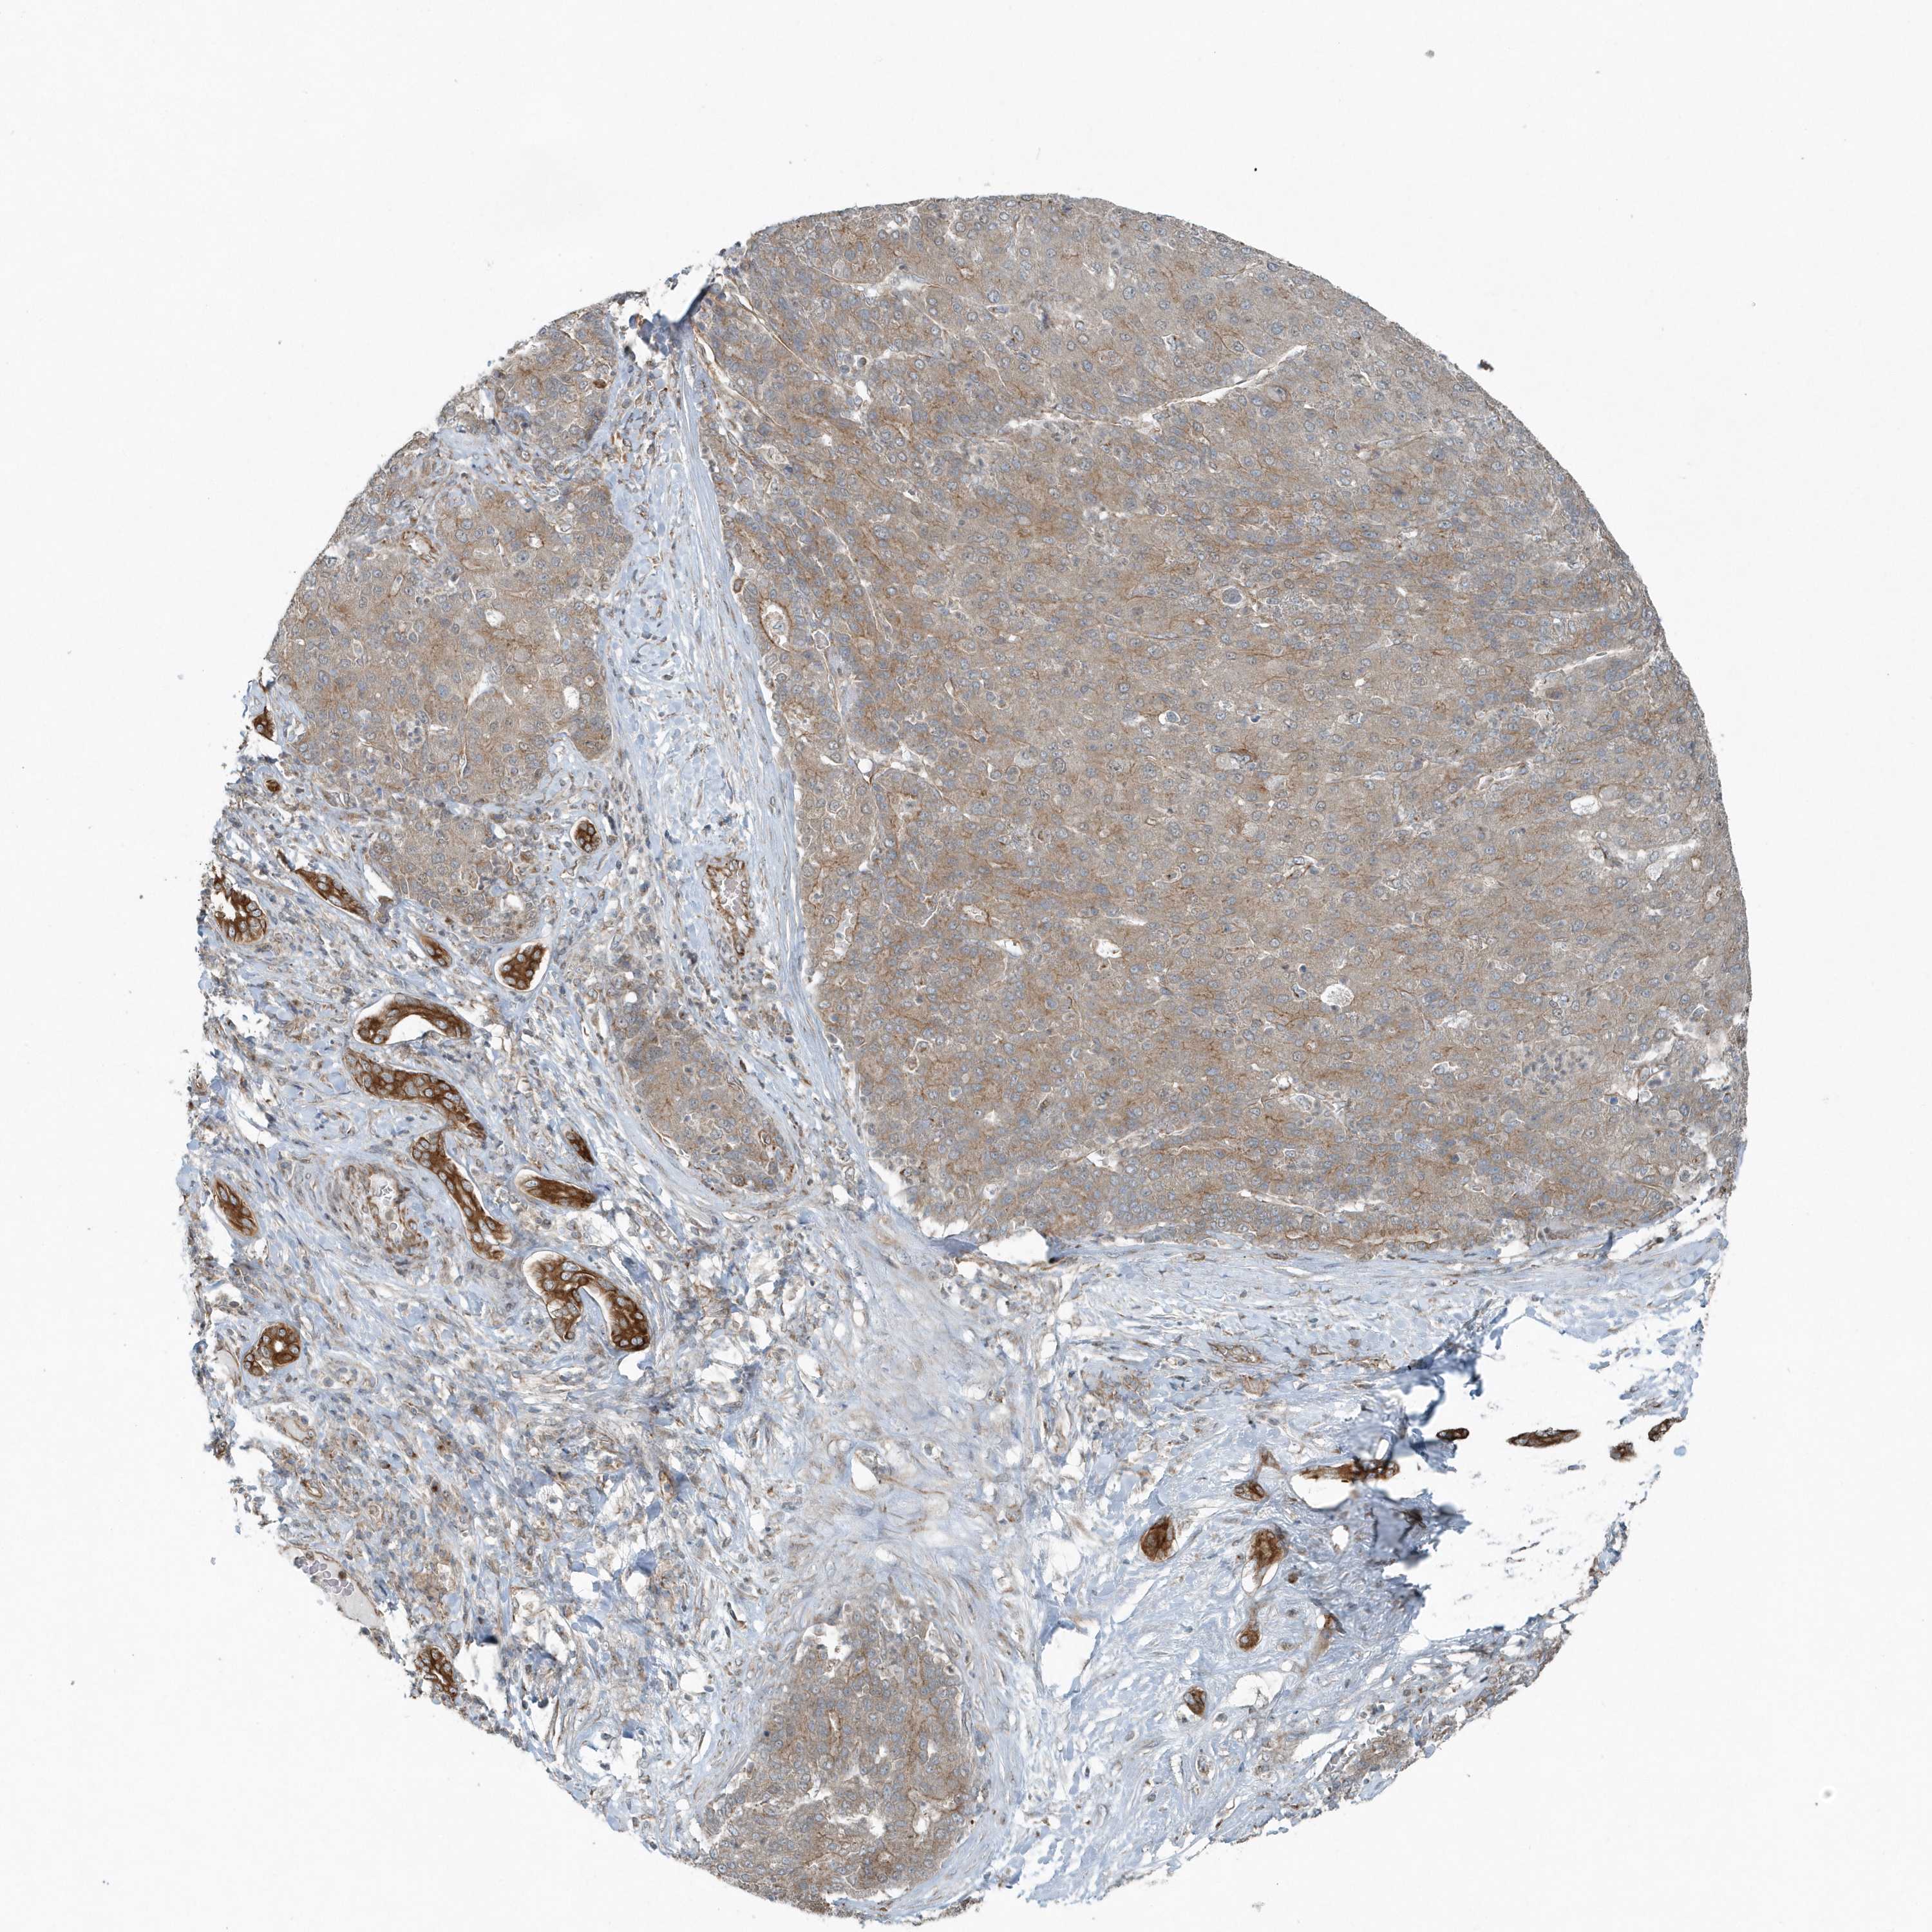

LIVER CANCER - Protein expressioni

A mouse-over function shows sample information and annotation data. Click on an image to view it in a full screen mode. Samples can be filtered based on level of antibody staining by selecting one or several of the following categories: high, medium, low and not detected. The assay and annotation is described here.

Note that samples used for immunohistochemistry by the Human Protein Atlas do not correspond to samples in the TCGA dataset.

Antibody stainingi

Antibody staining in the annotated cell types in the current human tissue is reported as not detected, low, medium, or high, based on conventional immunohistochemistry profiling in selected tissues. This score is based on the combination of the staining intensity and fraction of stained cells.

Each image is clickable and will lead to virtual microscopy that enables deeper exploration of all samples and also displays staining intensity scores, fraction scores and subcellular localization as well as patient and tissue information for each sample.

Antibody HPA035849

Antibody HPA035850

Staining

High

Medium

Low

Not detected

Intensity

Strong

Moderate

Weak

Negative

Quantity

>75%

75%-25%

<25%

None

Location

Nuclear

Cytoplasmic/membranous

Cytoplasmic/membranous,nuclear

Cholangiocarcinoma

Carcinoma, Hepatocellular, NOS